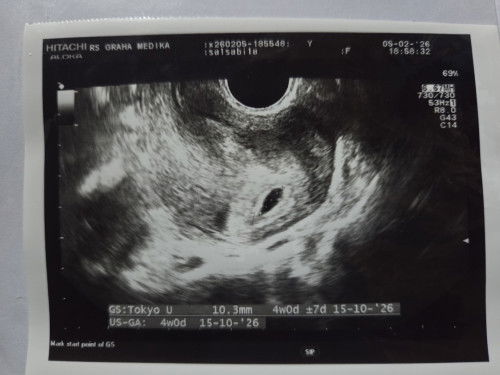

Dari kemarin mau USG maju mundur karena takut belum kelihatan, alhasil karena pengen dapet vitamin juga memutuskan usg. Diliat dari hasil USG kisaran 6-7 week dan Alhamdulillah udah ada detak jantungnya. Perkiraan HPL 1 november. Semangat buat para bunda semua 🫶🏻✨#firstmom #Sharingdong_Bund #askmommies